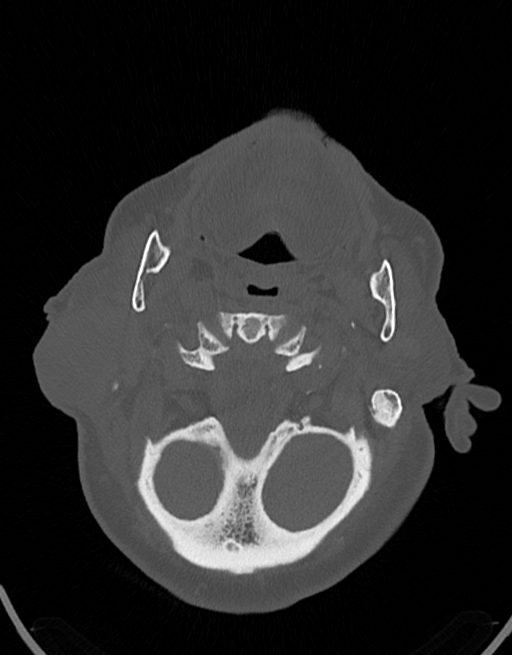

در سي تي اسکن اسپيرال نازو فارنکس با و بدون کنتراست (مولتي ديدکتور 16 با مقاطع ظريف و بازسازي هاي ساژيتال و کرونال):

– توده نسج نرمي به ابعاد mm 40 x 45 x 60 در ناحيه پاروتيد راست، با enhancement هتروژن پس از تزريق کنتراست مشهود است که مطرح کننده آدنوم پاروتيد مي باشد.

– شواهدي از تهاجم توده به استخوان و عروق اطراف مشهود نيست .

– کلسيفيکاسيون در ديواره شريان هاي کاروتيد دو طرف مشهود است .

– بررسي بافتي توده پاروتيد راست پيشنهاد مي شود .